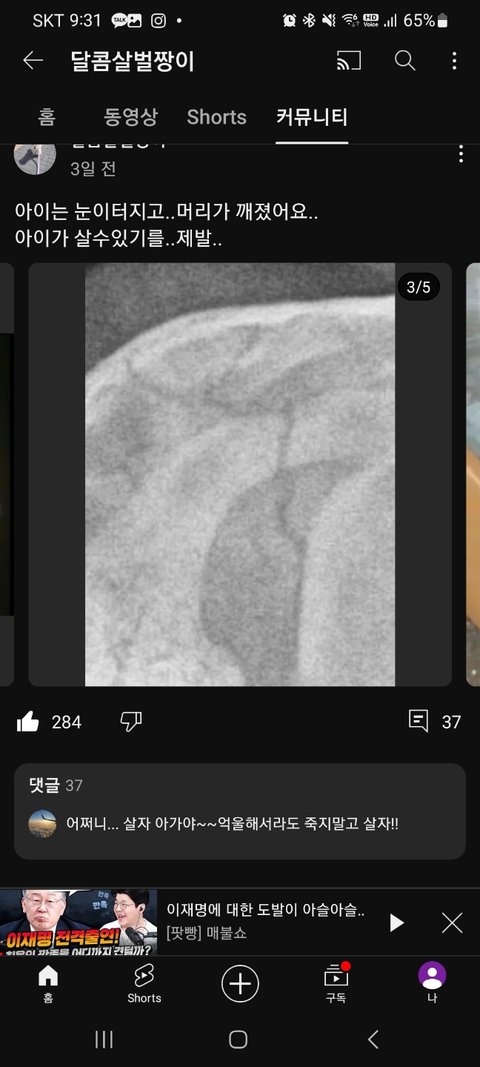

병원에 처음 왔을 때 폭력에 의한 피해가 너무커 최소한의 가능한 검사를 해본 결과 두개골은 수박이 갈라지듯 깨졌고 뇌출혈로 인해 간수치 1000이상, 척추 손상으로 기립 불가,